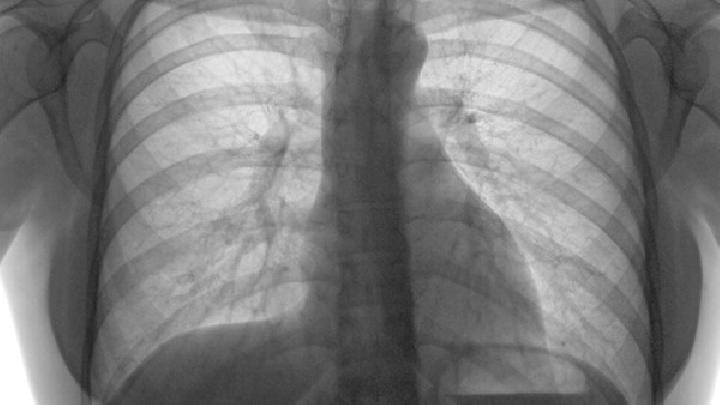

转移性肺癌系指任何部位的恶性肿瘤通过各种转移方式转移至肺部的肿瘤。约百分之六十以上的恶性肿瘤初次就诊时就有肿瘤转移,其中百分之三十到百分之五十肿瘤转移到肺部。不同部位的肿瘤转移到肺部的发生率不同,其中,甲状腺癌、乳腺癌、肾癌、绒毛膜癌、骨肉瘤发生率最高,可达百分之六十到百分之九十,肝癌、胃癌、结直肠癌、前列腺癌次之,为百分之三十五到百分之五十五,肺脏是骨肉瘤和软骨肉瘤惟一的转移器官。肺转移癌的发生率与原发肿瘤的生物学特性和机体的免疫功能状态有关。

患者王双喜,发病时65岁,于确诊肺癌前2个月无明显诱因突感胸闷气喘不适,自行治疗未见好转,于是到医院就行就诊,经过检查确诊为右肺小细胞肺癌,伴有肺内转移,另外患者心肺功能不全,伴慢性支气管炎感染。